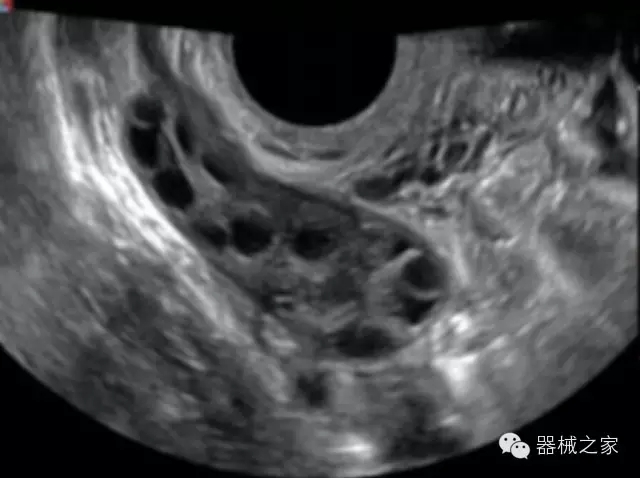

經(jīng)典產(chǎn)品:S8EXP

臨床圖片賞析

產(chǎn)品特點(diǎn)

·亞陣元技術(shù):獨(dú)有的亞陣元技術(shù),對(duì)獨(dú)立晶片做二次切割,減少旁瓣偽像,增加臨床診斷的準(zhǔn)確性;

·μ-Scan微米成像技術(shù):開立獨(dú)有的μ-Scan技術(shù),還原出真實(shí)細(xì)膩、層次對(duì)比優(yōu)異的二維圖像;

·高效3D/4D成像技術(shù):高速的4D幀頻,豐富的3D成像模式,智能斷層切片功能;